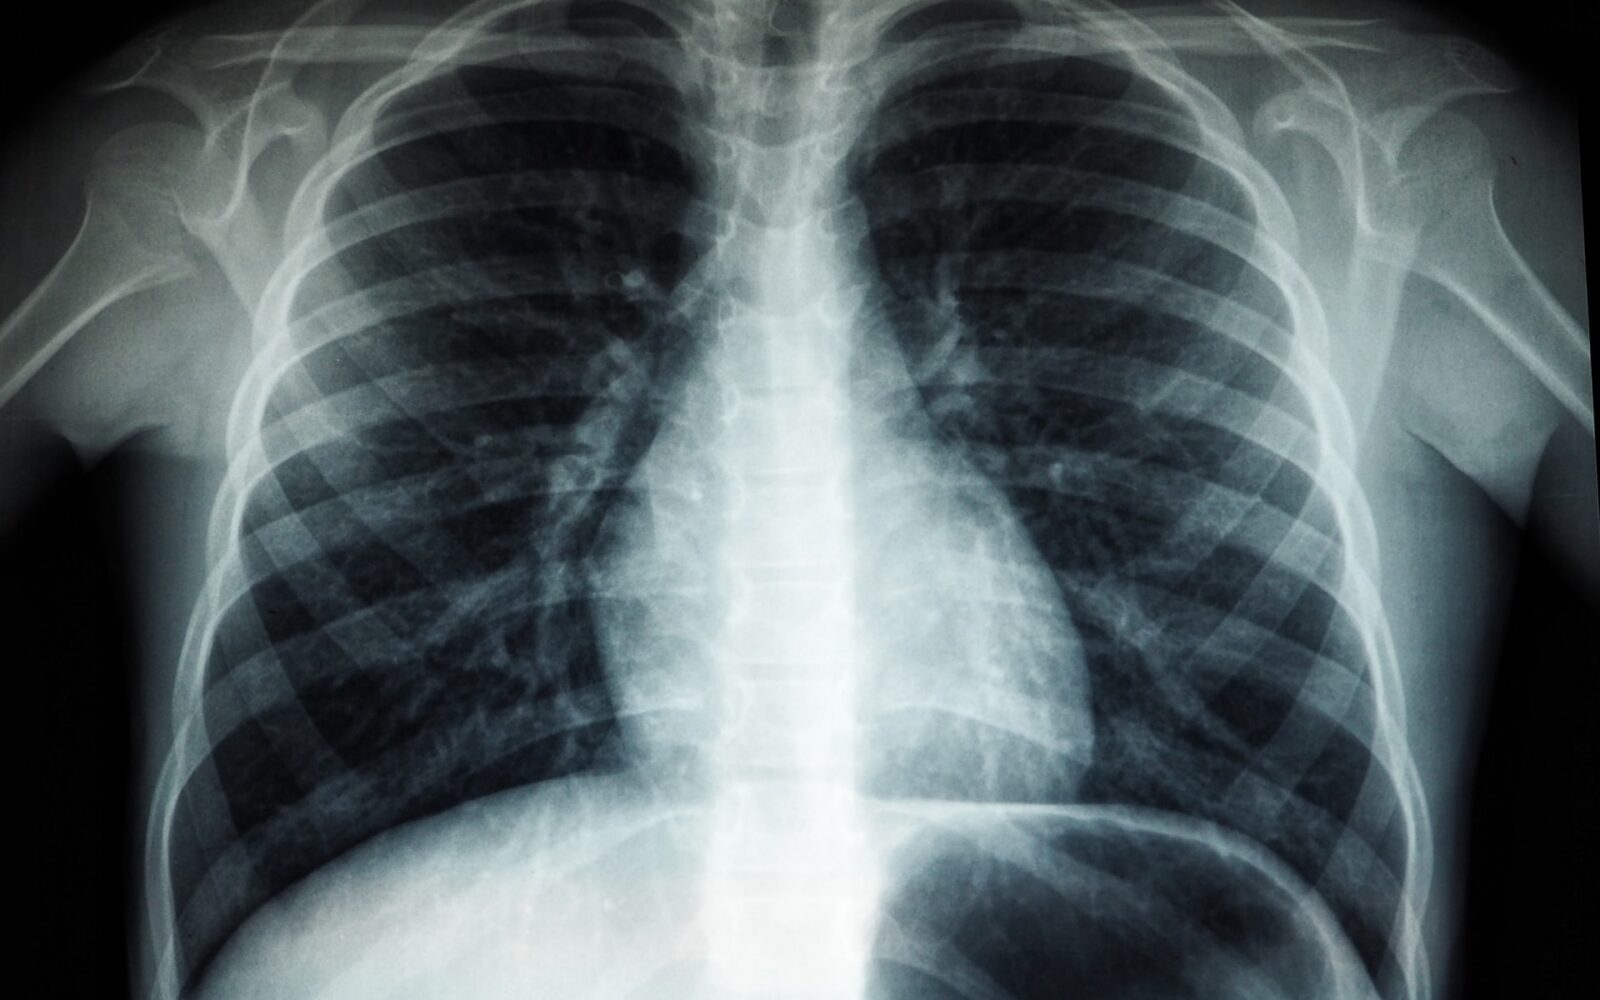

Studija otkrila na koji način koronavirus uništi pluća

Foto: Unsplash

Odavno znamo kakvu štetu težak oblik covida-19 može nanijeti plućima, ali točni razlozi tih promjena još se proučavaju. Studijom, koja bi mogla pomoći boljem liječenju zaraženih koronavirusom, znanstvenici u Njemačkoj pokazali su da je covid-19 često praćen teškim ožiljcima na plućnom tkivu.